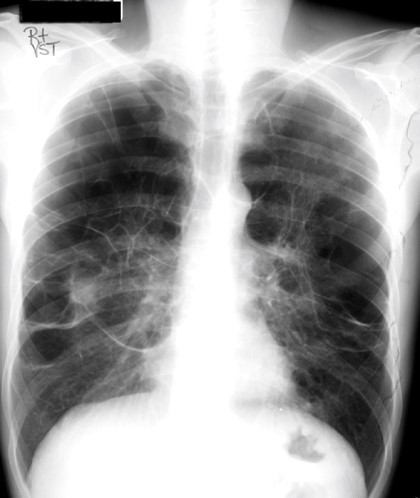

20yo with gradually increasing SOB & cough over 6 mo

View: PA

DX: metastatic disease